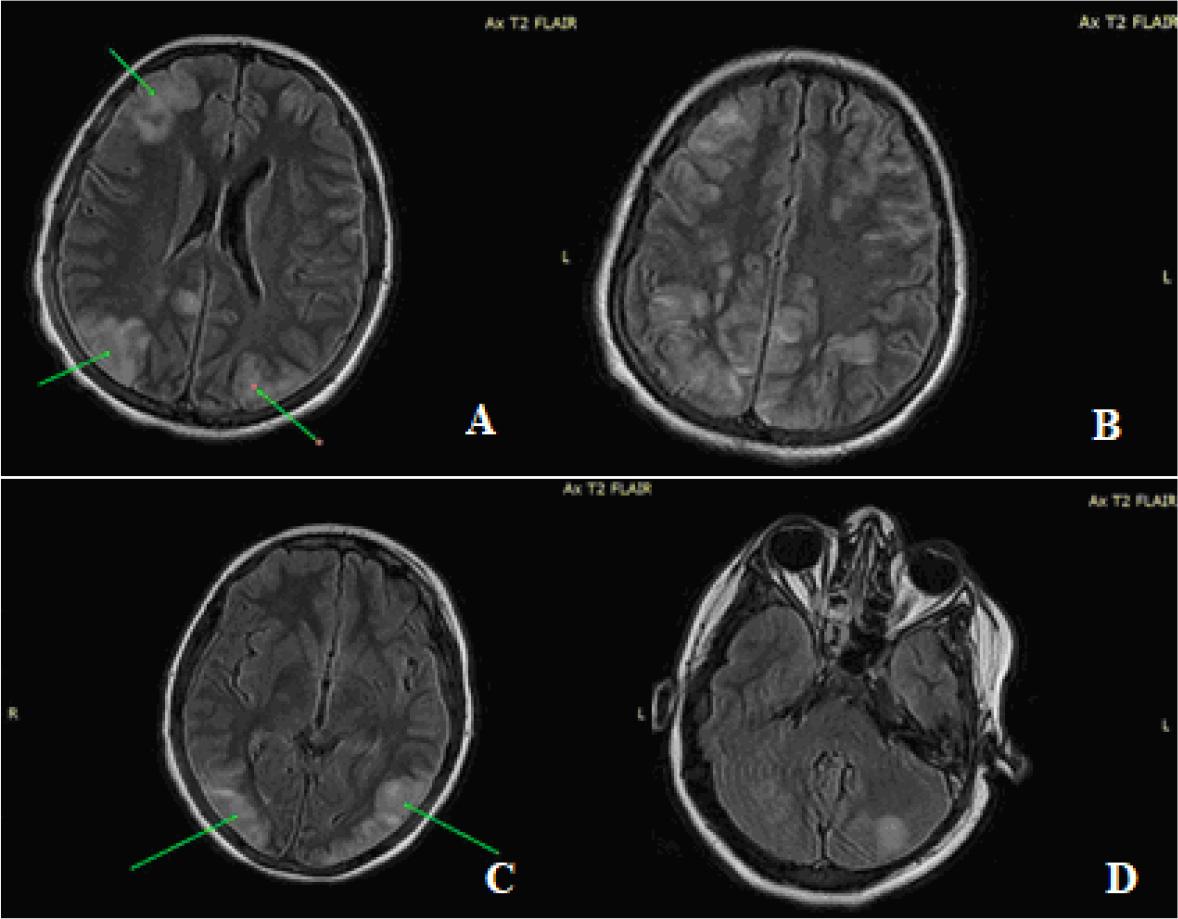

Fig. 1.